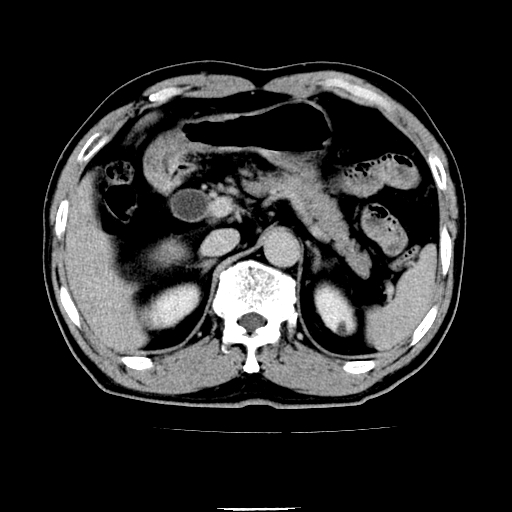

以下是引用chenqiong在2010-3-25 20:56:00的发言:[br]1、胆囊炎,胆囊息肉[br]2、肝内胆管及胆总管扩张,胆总管下端结石[br]3、十二指肠乳头旁憩室

以下是引用zxl51642在2010-3-26 10:47:00的发言:[br]胆囊炎,胆囊息肉,胆总管扩张,但未看到明显肿块,肝内胆管扩张不像恶性,炎性狭窄或阴性结石可能吧,建议mrcp,右肾小囊肿